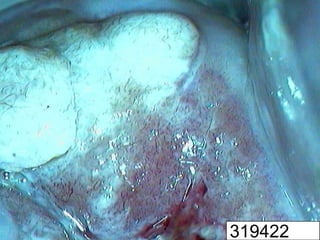

H-SIL and microinvasive

cervical cancers